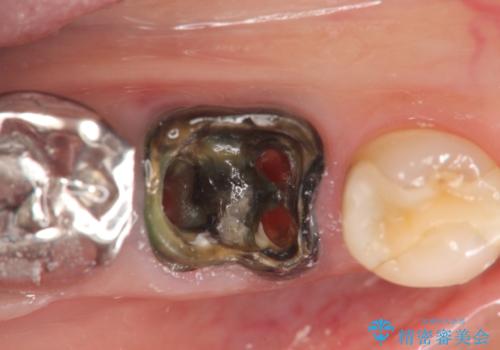

- 銀歯が取れてしまい、治療を希望され来院されました。

歯には大きな穴が開き、虫歯も大きくなってしまい残すことが難しいような状況であったため抜歯を余儀なくされました。